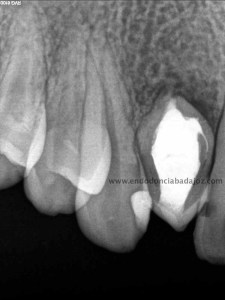

Como defensor del H de Ca ,en ciertas ocasiones, en este caso colocamos el mismo. En la siguiente cita, después de tallar el conducto, colocamos un sellado apical con cemento M.T.A. de varios milímetros y obturando con gutapercha inyectada con la pistola Obtura II.